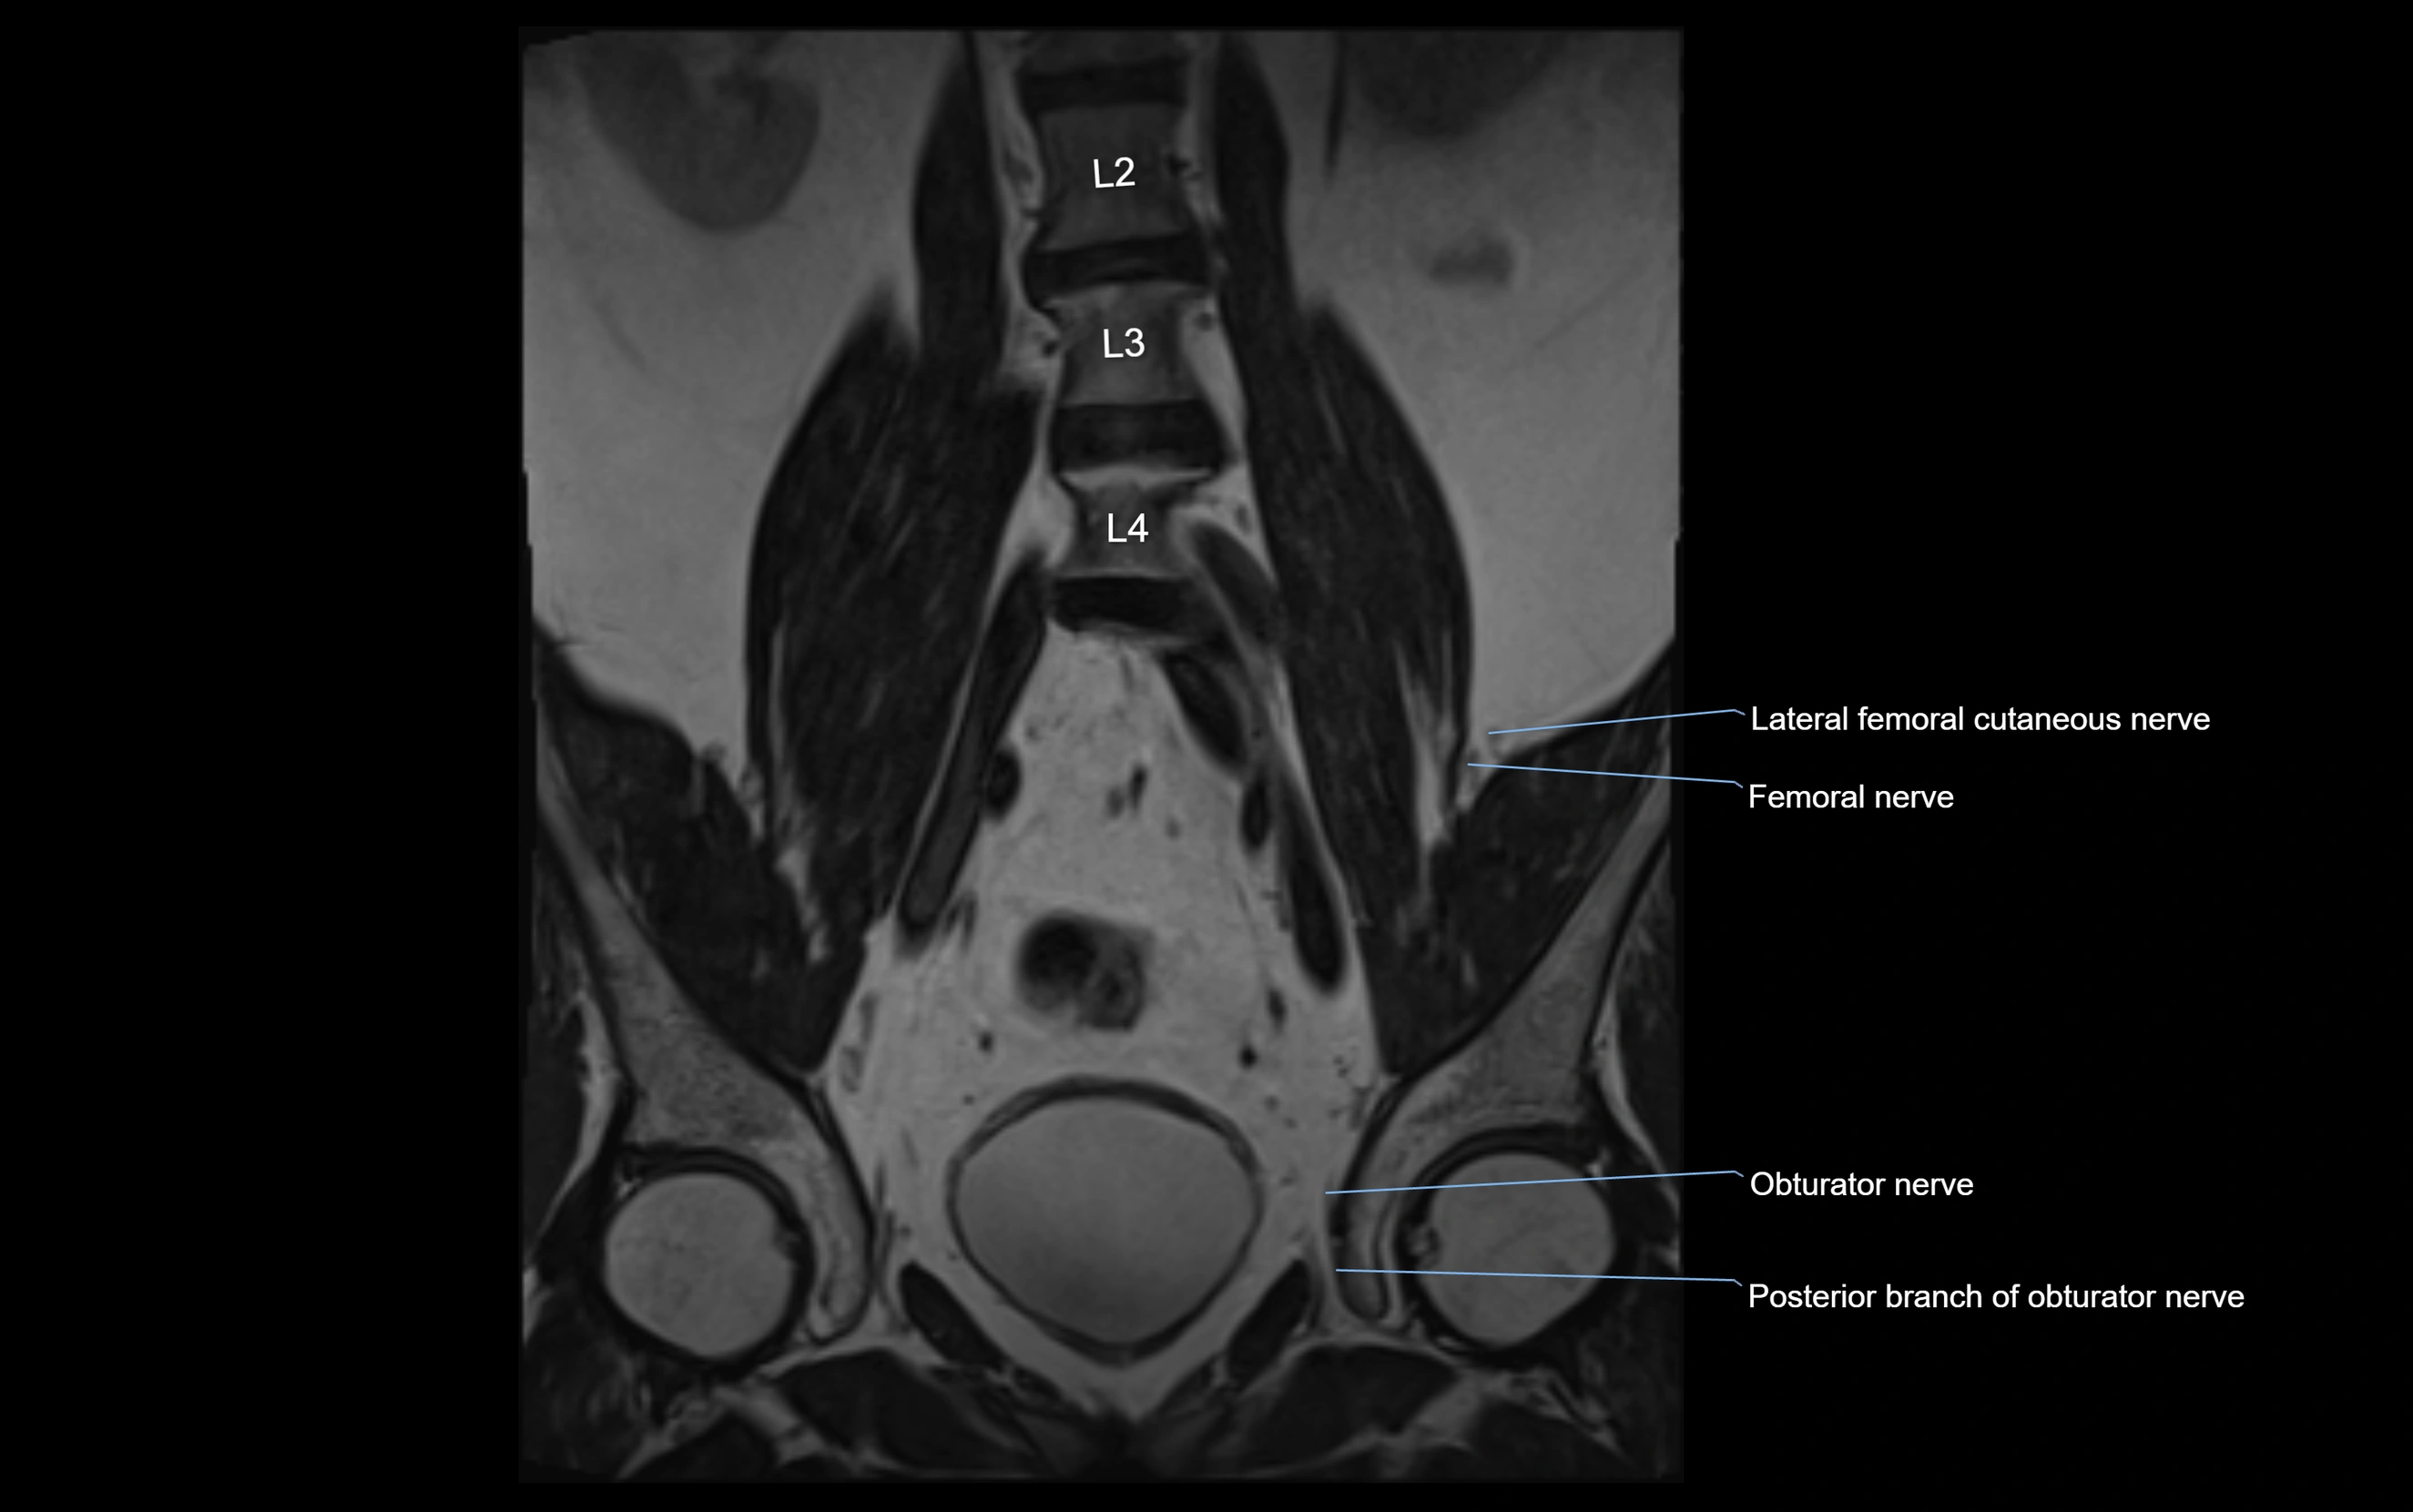

MRI image

image